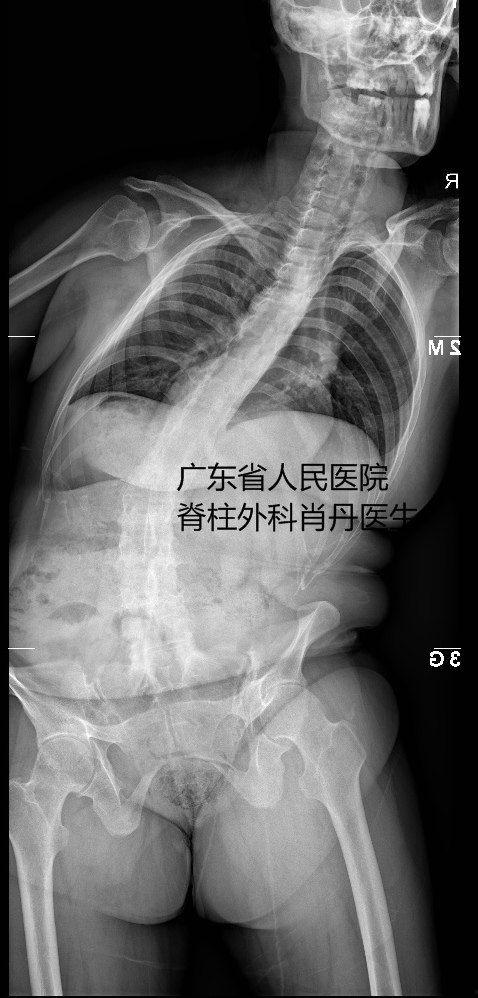

手术过程中,医生会根据患者的具体情况,选择合适的手术方式。常见的手术方法有:脊柱融合术、脊柱截骨术、脊柱侧弯矫正术等。这些手术都需要在全身麻醉下进行,患者将在无知觉的状态下完成这场与病痛的较量。